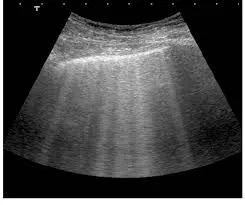

O paciente está congesto? O que realmente ajuda na prática?

O paciente está congesto? O que realmente ajuda na prática?